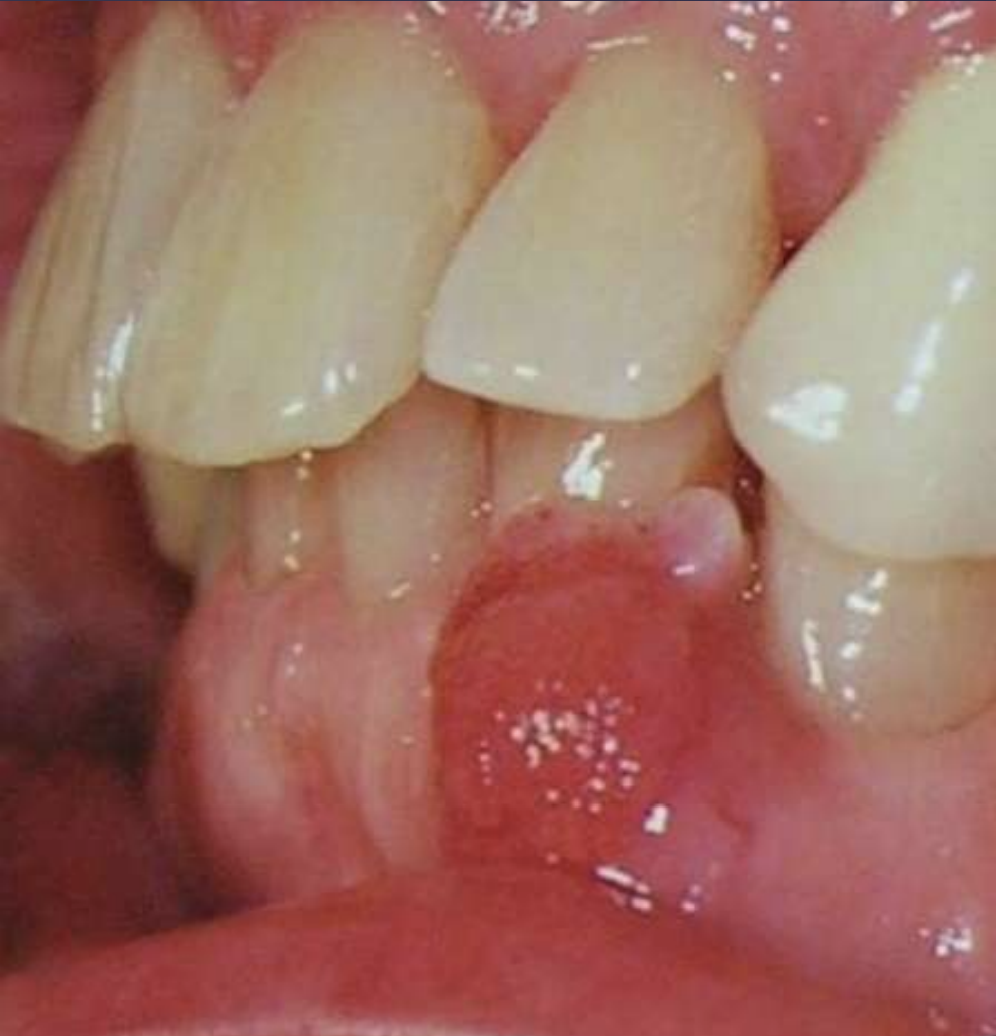

• Painless, non-ulcerated gingival nodule

• Resembles pyogenic granuloma or fibroma

• Usually < 1.5cm

• Superficial alveolar bone may be eroded

What benign tumor?

Peripheral Ameloblastoma